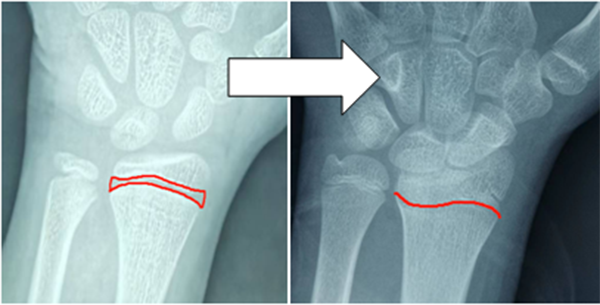

未成熟的長骨在結(jié)構(gòu)上包括骨骺和骨干兩個(gè)部分。骨骺與干骺端之間的軟骨,呈現(xiàn)在骨齡片中是透光帶,我們稱之為骺板或生長板,其本質(zhì)是軟骨,正是軟骨的存在,骨才能不斷生長變長,人才能長高。隨著青春期來臨,性激素分泌增加,生長板逐漸鈣化,被骨組織取代,剩下一條緊密的縫,骨齡片中透光帶模糊以至消失,也就是家長們逐漸熟知的“骨骺線閉合”,這標(biāo)志著長骨停止生長,人的身高增長趨于終止,如下圖。